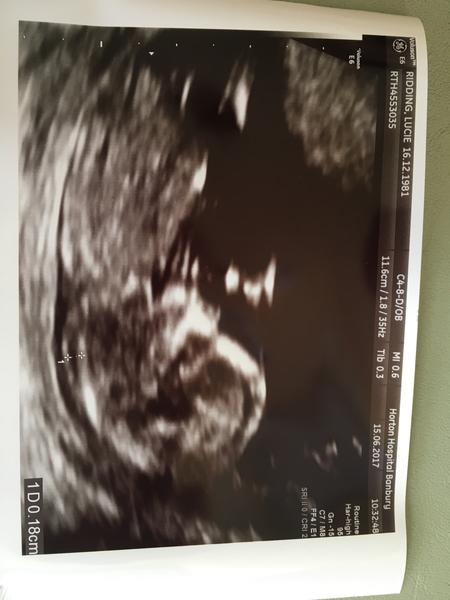

Tak jdu od doktora, porad v brise tekutina a zvetsene vajecniky a porad hodne pit. Ukazoval mi malou tecku, coz by mohl pry byt gestacni vacek, ale pry se nemam radovat, nic to byt nemusi.

@luciebx Luci, neboj, všechno bude v pořádku, teším se na fotku, jupííí🙂